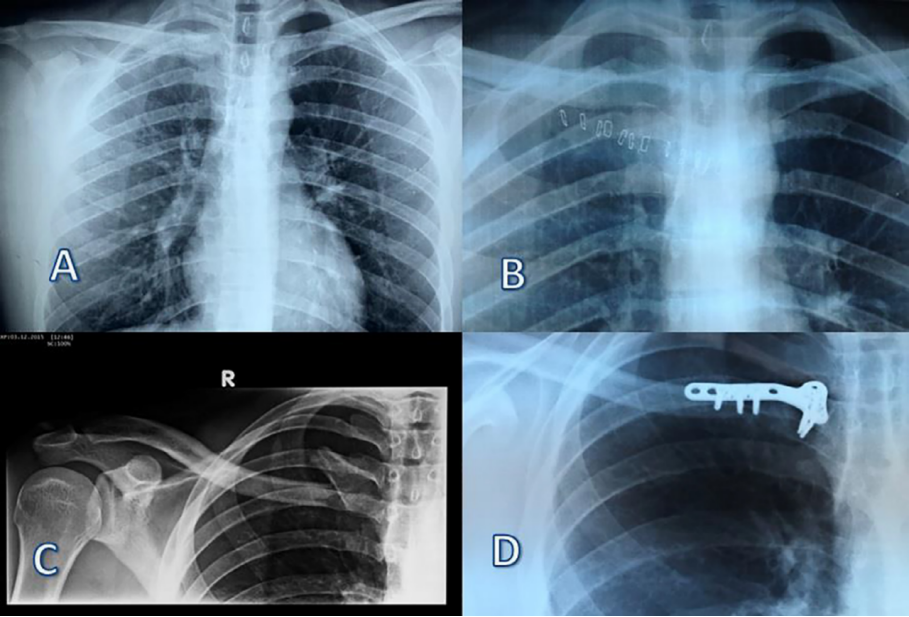

图3所示

A:术前正位胸部x线片示胸锁关节不对称,提示胸锁关节脱位。

B:术后胸片。胸锁关节是对称的。

C:术前正位x线片:胸锁关节前脱位,伴锁骨内侧端骨折。

D:术后1年胸片。骨折愈合,胸锁关节复位。